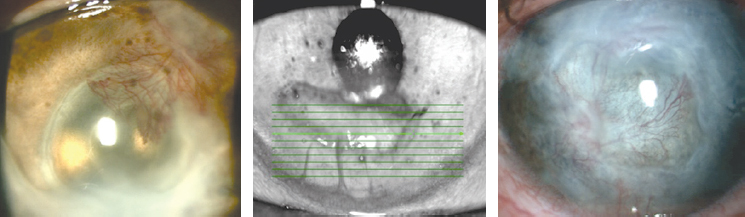

Измерения ВГД проведены у 39 пациентов с глаукомой и/или катарактой (22 женщины, 17 мужчин, средний возраст 62,34 ± 9,1 года, от 43 до 78 лет), с изменениями роговицы вследствие различной офтальмопатологии: посттравматические рубцы (5 глаз); кератотомические рубцы после рефракционных хирургических вмешательств, в том числе после сквозной кератопластики (6 глаз); дефекты роговицы в исходе язвенного процесса различной этиологии (4 глаза); эрозии роговицы (12 глаз); буллёзная кератопатия (7 глаз); деформации и лейкомы после хирургического лечения птеригиума или воздействия инфекционного агента (5 глаз). У 28 пациентов диагностирована первичная глаукома I–IV стадий или вторичная (постувеальная, неоваскулярная и др.), на 18 глазах ранее, в сроки от 15 лет до 6 мес., были выполнены 1–2 антиглаукомные операции, однако в зонах хирургического вмешательства не выявлялись фильтрационные подушки, которые могли бы повлиять на конгруэнтность поверхности глазного яблока и верхнего века. В 16 случаях пациенты получали местную гипотензивную терапию в разных сочетаниях лекарственных средств. Все глаза в различные сроки получали противовоспалительную и регенерирующую терапию по поводу заболевания роговицы. Основным из критериев включения в исследование пациентов было наличие патологии роговицы, препятствовавшей проведению пневмотонометрии и контактных методов измерения офтальмотонуса (рис. 2).

Рис. 2. Патологические изменения роговицы у пациентов

Fig. 2. Pathological changes of the cornea in patients